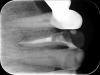

Kivilgar Опубликовано 8 ноября, 2013 Поделиться Опубликовано 8 ноября, 2013 2.jpg1.jpg3.jpg надо сохранять)Создается ощущение, что в отмеченной области недовычистили старый силер, потому и вид в апикальной части не очень. http://i017.radikal.ru/1311/25/e13b89182a9d.jpghttp://s43.radikal.ru/i101/1311/51/ab761e18da1e.jpghttp://s017.radikal.ru/i443/1311/e3/43cda8e1efec.jpg 1 Ссылка на комментарий

Ildarad Опубликовано 8 ноября, 2013 Поделиться Опубликовано 8 ноября, 2013 да, думаю так и есть Ссылка на комментарий

Kivilgar Опубликовано 8 ноября, 2013 Поделиться Опубликовано 8 ноября, 2013 да, думаю так и есть Бывает, что поделаешь Ссылка на комментарий